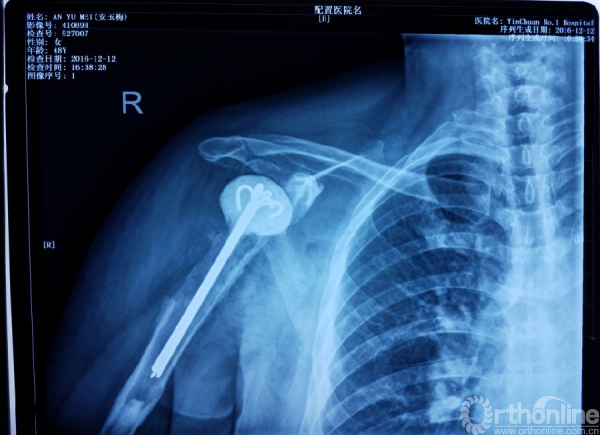

术后X线

1.抗生素骨水泥占位器植入

2.不锈钢克氏针+抗生素骨水泥

3.柄部没有骨水泥,利于引流,头部较原有假体头部偏大,减少挛缩,占位关节腔,颈干角及后倾维持

4.用肌腱缝线固定减少排斥

5.后内侧结构尽量不去干扰,防止出现神经血管损伤。